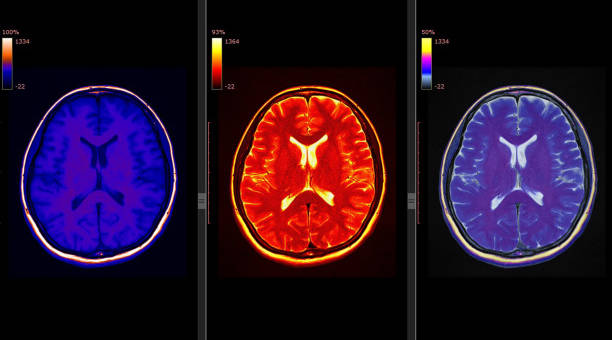

뇌경색 후유증은 심각한 장애를 남길 수 있는 신체적, 정신적 문제를 야기할 수 있는 중요한 주제입니다.

뇌경색 후유증은 다양한 증상을 유발할 수 있습니다. 이러한 증상은 흔히 다음과 같이 나눌 수 있습니다.

1. 전두엽 손상

뇌경색 후, 이마 부위에 손상이 생기면 하체의 힘이 약해질 수 있습니다. 이로 인해 환자는 걷거나 움직일 때 한 쪽으로 기울거나 반쪽의 마비가 발생할 수 있습니다. 대소변의 장애, 성격 변화, 사고력 저하, 집중력 감소 등과 같은 부작용도 나타날 수 있습니다.

2. 두정엽 손상

두정엽 손상은 실인증과 관련이 있습니다. 환자는 물체를 만져보면 물체를 정확히 인식하지 못하거나, 반대편의 손으로 만졌을 때 자기 몸이 아닌 타인의 몸으로 인식할 수 있습니다.

3. 측두엽 손상

측두엽 손상은 기억력 저하, 청력 감소, 언어 기능 저하 등을 포함합니다. 이 증상은 혈관성 치매로 진행할 수 있으며, 가장 심각한 경우에는 실명에 이를 수도 있습니다.

4. 뇌관 부위 손상

뇌관은 우리 몸의 생체 징후를 담당하는 부위로, 이상이 있는 경우 음식을 적절히 소화하지 못하게 되어 식사에 어려움을 겪을 수 있습니다. 호흡 장애도 발생할 수 있어 인공호흡 장치가 필요할 수 있습니다.